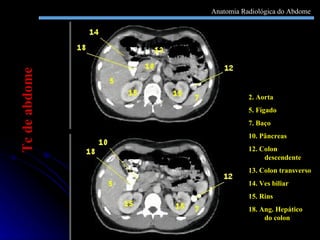

2. Aorta 5. Fígado 7. Baço 10. Pâncreas 12. Colon descendente 13. Colon transverso 14. Ves biliar 15. Rins 18. Ang. Hepático do colon Tc de abdome Anatomia Radiológica do Abdome

2. Aorta 5.Fígado 7. Baço 10. Pâncreas 12. Colon descendente 13. Colon transverso 14. Ves biliar 15. Rins 18. Ang. Hepático do colon Tc de abdome Anatomia Radiológica do Abdome